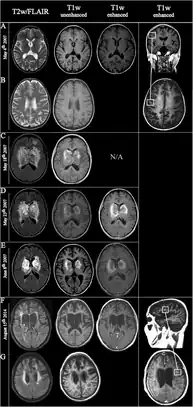

Laboratory studies that support diagnosis of AHL are: peripheral leukocytosis, cerebrospinal fluid (CSF) pleocytosis associated with normal glucose and increased protein. On magnetic resonance imaging (MRI), lesions of AHL typically show extensive T2-weighted and fluid-attenuated inversion recovery (FLAIR) white matter hyperintensities with areas of hemorrhages, significant edema, and mass effect.[60]